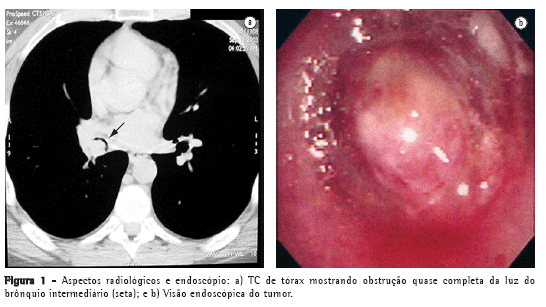

Um paciente masculino de 36 anos, não tabagista, internou-se para investigação de tosse crônica e sibilância. O exame físico demonstrou sibilo expiratório à direita. A radiografia simples de tórax evidenciou atelectasia do lobo inferior direito, enquanto a tomografia de tórax demonstrou a presença de uma imagem endobrônquica (Figura 1a). A broncoscopia identificou uma lesão vegetante que ocluía completamente o brônquio intermediário (Figura 1b) e a biópsia sugeriu o diagnóstico de hemangioma. O paciente foi estadiado sistematicamente devido à hipótese de se tratar de uma neoplasia brônquica. Sem evidência de comprometimento loco-regional ou à distância, o paciente foi submetido a uma toracotomia lateral direita para ressecção do lobo inferior. Devido a sua extensão endobrônquica, com comprometimento do brônquio intermediário e não invasão do brônquio lobar médio, decidiu-se realizar lobectomia inferior com ressecção parcial do brônquio intermediário e uma reconstrução com anastomose entre a parte proximal do brônquio intermediário e o brônquio lobar médio. O paciente teve uma evolução pós-operatória sem intercorrências e recebeu alta no quinto dia pós-operatório. O tumor originava-se no brônquio segmentar superior do lobo inferior direito (Figura 2). O diagnóstico anátomo-patológico foi de pseudotumor inflamatório do tipo fibrohistiocítico (Figura 3), confirmado por imunohistoquímica.